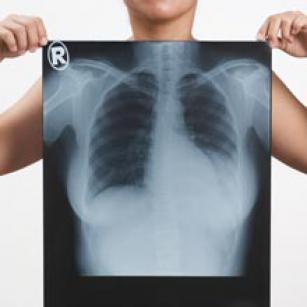

Getting into the chest x-ray—the importance of greyscale (part 1) 13th Oct 2015 - Julian Dobranowski, MD, FRCPC In this video, you will learn how different tissue densities create different shades of grey on a chest x-ray. You’ll ...